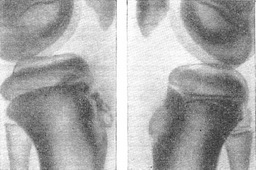

Шлаттера хвороба супроводжується відривом дрібних: ядерець окостеніння горбистості великогомілкової кістки (рис. 1) або їх частинок, розривами частини волоконец власної зв'язки надколінка в місцях прикріплення до апофизу, місцевими дрібними крововиливами, асептичними послетравматическими запаленнями, іноді рецидивуючими, в області слизових сумок і в першу чергу підшкірної поднадколенниковой (bursa subcutanea infrapatellaris) і поднадколенниковой глибокої (bursa profunda infrapatellaris). Шлаттера хвороба виникає, як правило, тільки в період росту, частіше у хлопчиків 12-14 років, особливо у спортсменів. В області горбистості великогомілкової кістки поволі з'являється бліда болюча при тиску плотноеластіческая припухлість, крізь яку прощупується твердий виступ. Нерідко ураження двостороннє. Місцеві болі можуть виникати спонтанно, але частіше викликаються при випадковому місцевому тиску або ударі і рухах, пов'язаних з розгинанням колінного суглоба.

![]() Рис. 1. Хвороба Шлаттера. Травматична зміщення частини ядер окостеніння бугристостей великогомілкових кісток, більш виражене зліва. |

На початку хвороби на бічній рентгенограмі проксимальної частини гомілки визначається нормальний стан ядра (або ядер) окостеніння горбистості великогомілкової кістки, суцільним або переривчастим хоботком спускається від епіфіза (ця картина може бути асиметричної на обох кінцівках); видно лише потовщення м'якого покриву горбистості і підвищення нижньої межі чотирикутного просвітлення (обумовленого жировою тканиною в передній частині суглоба) внаслідок запального збільшення глибокої поднадколенниковой сумки. В динаміці спостереження виявляється зсув 1-3 тіней дрібних кісткових тілець, часто неправильної форми, з групи ядер окостеніння горбистості кпереди і догори, зазвичай до 2-5 мм; часто все ядро окостеніння трохи зміщується допереду на 1-3 мм внаслідок реактивного потовщення підлягає хряща. Обриси ядерець окостеніння і підлягає ділянки метафіза великогомілкової кістки можуть ставати нерівними, а трабекулярная структура може бути нечіткою. З часом зміщені кісткові тільця можуть розсмоктуватися; частіше ж вони зливаються з іншими частинами ядра апофіза в єдиний кістковий конгломерат, широким підставою виходить з горбистості великогомілкової кістки і грубим, нерівним, іноді шиповидным виступом спрямований догори і трохи вперед, де він триває до власної зв'язки надколінка (рис. 2). Іноді ж у дистальній частині останньої, поблизу горбистості, помітний ізольований фокус давнього окостеніння зв'язки округлої або неправильної форми діаметром не більше 4-6 мм.